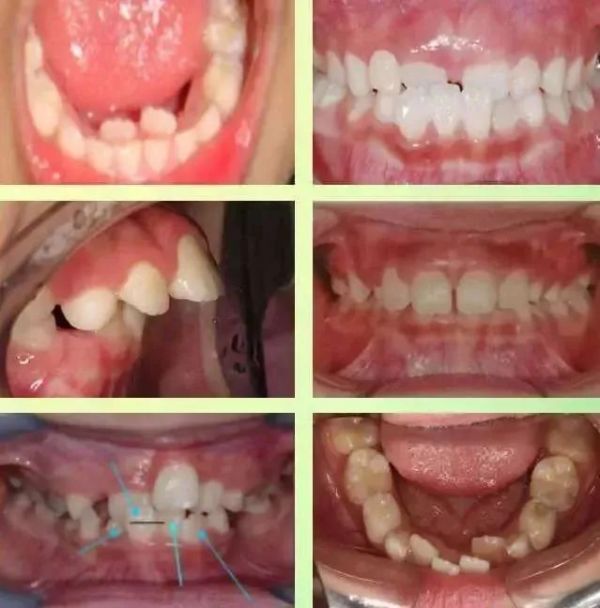

我们来看一组照片:

在儿童生长早期,由于儿童的不良习惯,容易出现牙齿不齐,深覆合,地包天等口腔问题。

哪些牙齿不齐需要早期矫正

牙齿不齐是指儿童生长发育过程中,由先天的遗传因素或后天的环境因素造成的牙齿排列不齐、上下牙弓牙颌关系异常、颌骨大小形态位置异常、面部畸形等问题。有以下几种情况就需要注意了。

深覆盖(龅牙)

上颌前牙向前异常突起,情况严重者就是我们通常所说的龅牙。

深覆颌

上牙包住下牙的范围过大,情况严重者甚至可以咬到下牙牙龈。

反颌(地包天)

下牙包住上牙,可以造成月牙脸,影响颜面美观。

开颌

牙齿咬合或前伸时,上下牙在垂直方向上不能接触。

牙齿拥挤

牙量大于骨量空间不够导致牙齿排列不整齐呈重叠拥挤状态。